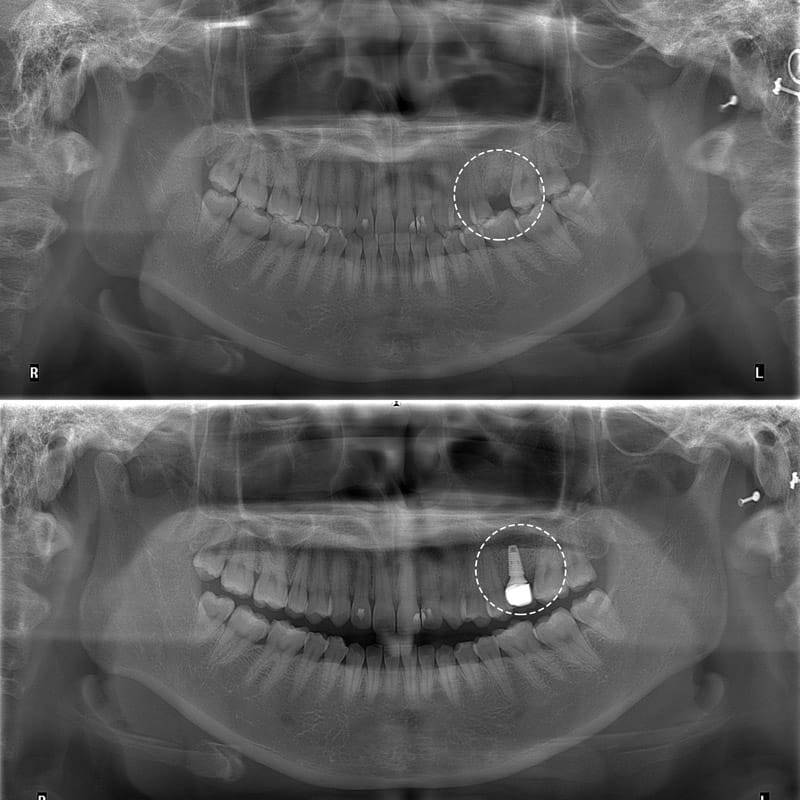

Cấy Ghép Implant cho răng số 6 bị mất

Mất răng số 6

Tác hại việc mất răng 6

Cấy ghép Implant là kỹ thuật đặt một trụ titanium vào xương hàm để thay thế chân răng thật, sau đó gắn mão sứ lên trên, giúp phục hồi cả thân và chân răng.

Thăm khám – chụp CT 3D – lập kế hoạch điều trị cá nhân hóa.

Đặt trụ implant trong điều kiện vô khuẩn tuyệt đối.

Tái khám định kỳ và gắn răng sứ sau 2–3 tháng.